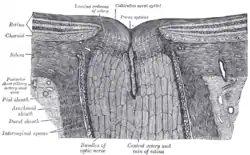

Iris, front view The terminal portion of the optic nerve and its entrance into the eyeball, in horizontal section

The terminal portion of the optic nerve and its entrance into the eyeball, in horizontal section The interior of the posterior half of the left eyeball